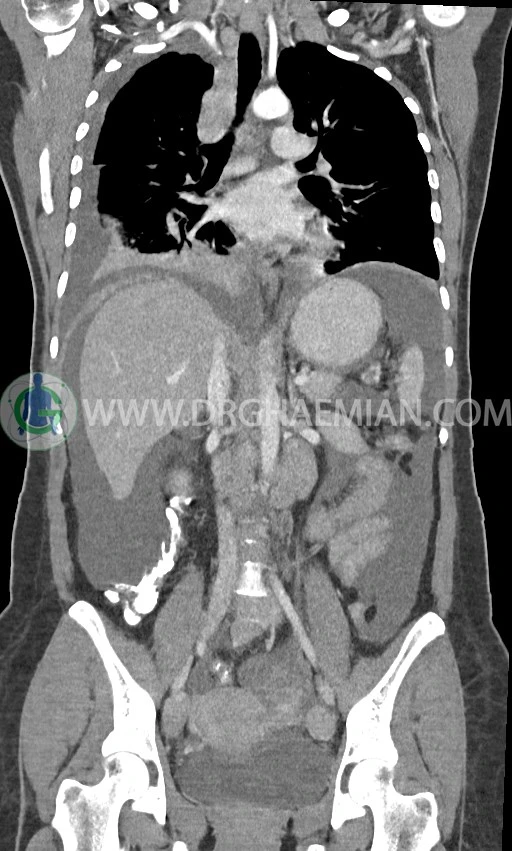

در سی تی اسکن اسپیرال ریه، مدیاستن و شکم و لگن با کنتراست خوراکی و وریدی (مولتی دیدکتور 16 با مقاطع ظریف و بازسازی های ساژیتال و کرونال) :

pleural effusion قابل توجه دوطرفه همراه با passive collapse سگمان های بازال (با شدت بیشتر در سمت راست)

اسیت قابل توجه در حفره شکم و لگن

انفیلتراسیون تومورال در قسمت های مختلف اومنتوم (omental cake)، به ویژه در قسمت تحتانی حفره شکم و لگن

توده سالید – سیستیک به ابعاد 40x60mm در تخمدان چپ و به ابعاد 20x40mm در تخمدان راست و

لنفادنوپاتی فراوان در اطراف آئورت و IVC با حداکثر SAD= 25mm در دیواره دو طرف حفره لگن با حداکثر SAD= 20mm

مشهود است.